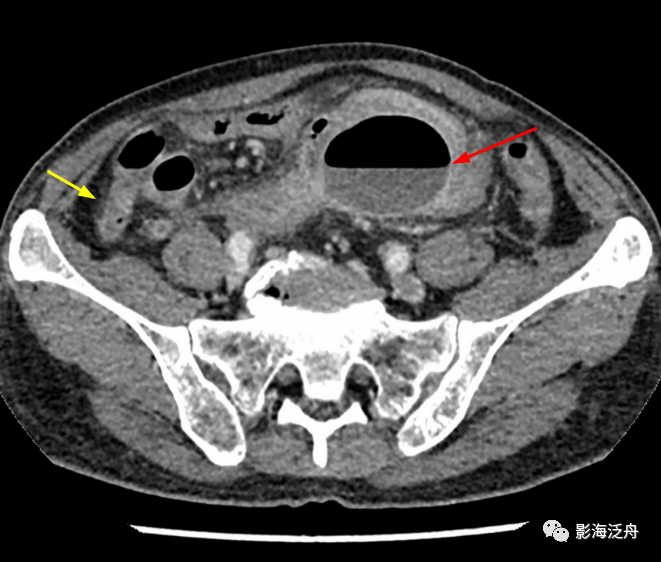

小心误诊这可不是急性阑尾炎

图片尺寸679x547